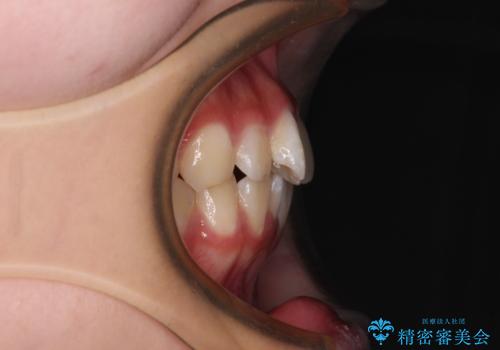

- 上下前歯のねじれを気にして来院された患者様です。

ワイヤー矯正でもマウスピース矯正でも対応可能でしたが、マウスピース矯正の自己管理が面倒であること、上顎前歯の捻転が著しいことから、ワイヤー矯正での治療を希望されました。